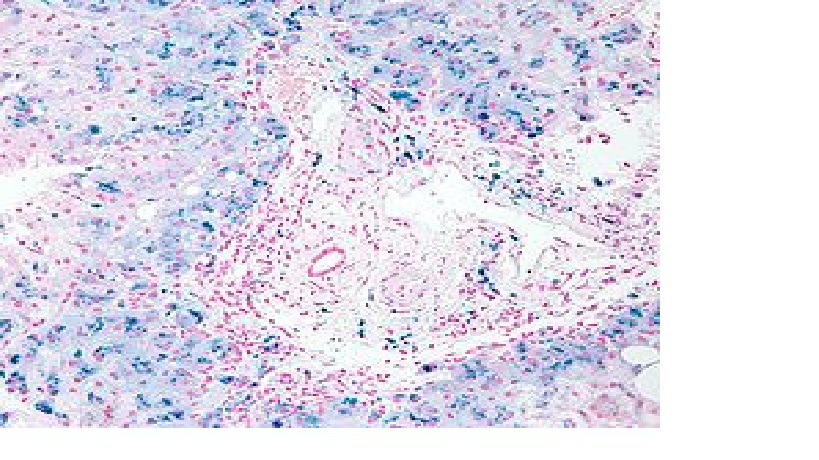

Hemochromatoza jest chorobą metaboliczną związaną z zaburzonym wchłanianiem żelaza i jego nadmierną kumulacją w organiźmie. Objawowa hemochromatoza prowadzi do powkłań narządowych w postaci uszkodzenia wątroby (marskość, rak), cukrzycy, kardiomiopatii, niewydolności gruczołów wydzielania wewnętrznego oraz artropatii. Postać pierwotna choroby (PH) dziedziczona jest autosomalnie recesywnie i związana z mutacją w obrębie genu HFE. Fenotyp hemochromatozy ujawnić może ososba posiadająca od każdego z rodziców (nosicieli mutacji) kopię zmutowanego genu – najczęściej C282Y. Rzeczywista częstość artropatii u chorych na PH nie jest dokładnie znana, podobnie jak patogeneza zmian stawowych. Znaczenie mogą mieć tutaj: stres oksydacyjny związany z obecnością jonów żelaza; stymulacja komórek błony maziowej; promocja krystalizacji dwuwodnego pirofosforanu wapnia prowadzace do zmian degeneracyjnych chrząstki i stawu. Najczęściej zmiany w układzie ruchu, w przebiegu PH, występują pod postacią artralgii oraz zmian przypominających chorobę zwyrodnieniową stawów i współistnieć mogą z chondrokalcynozą. Radiologicznie zmiany odpowiadaja występującym we wspomnianych jednostkach chorobowych, z predyspozyją do zajmowania 2 i 3 stawu MCP.